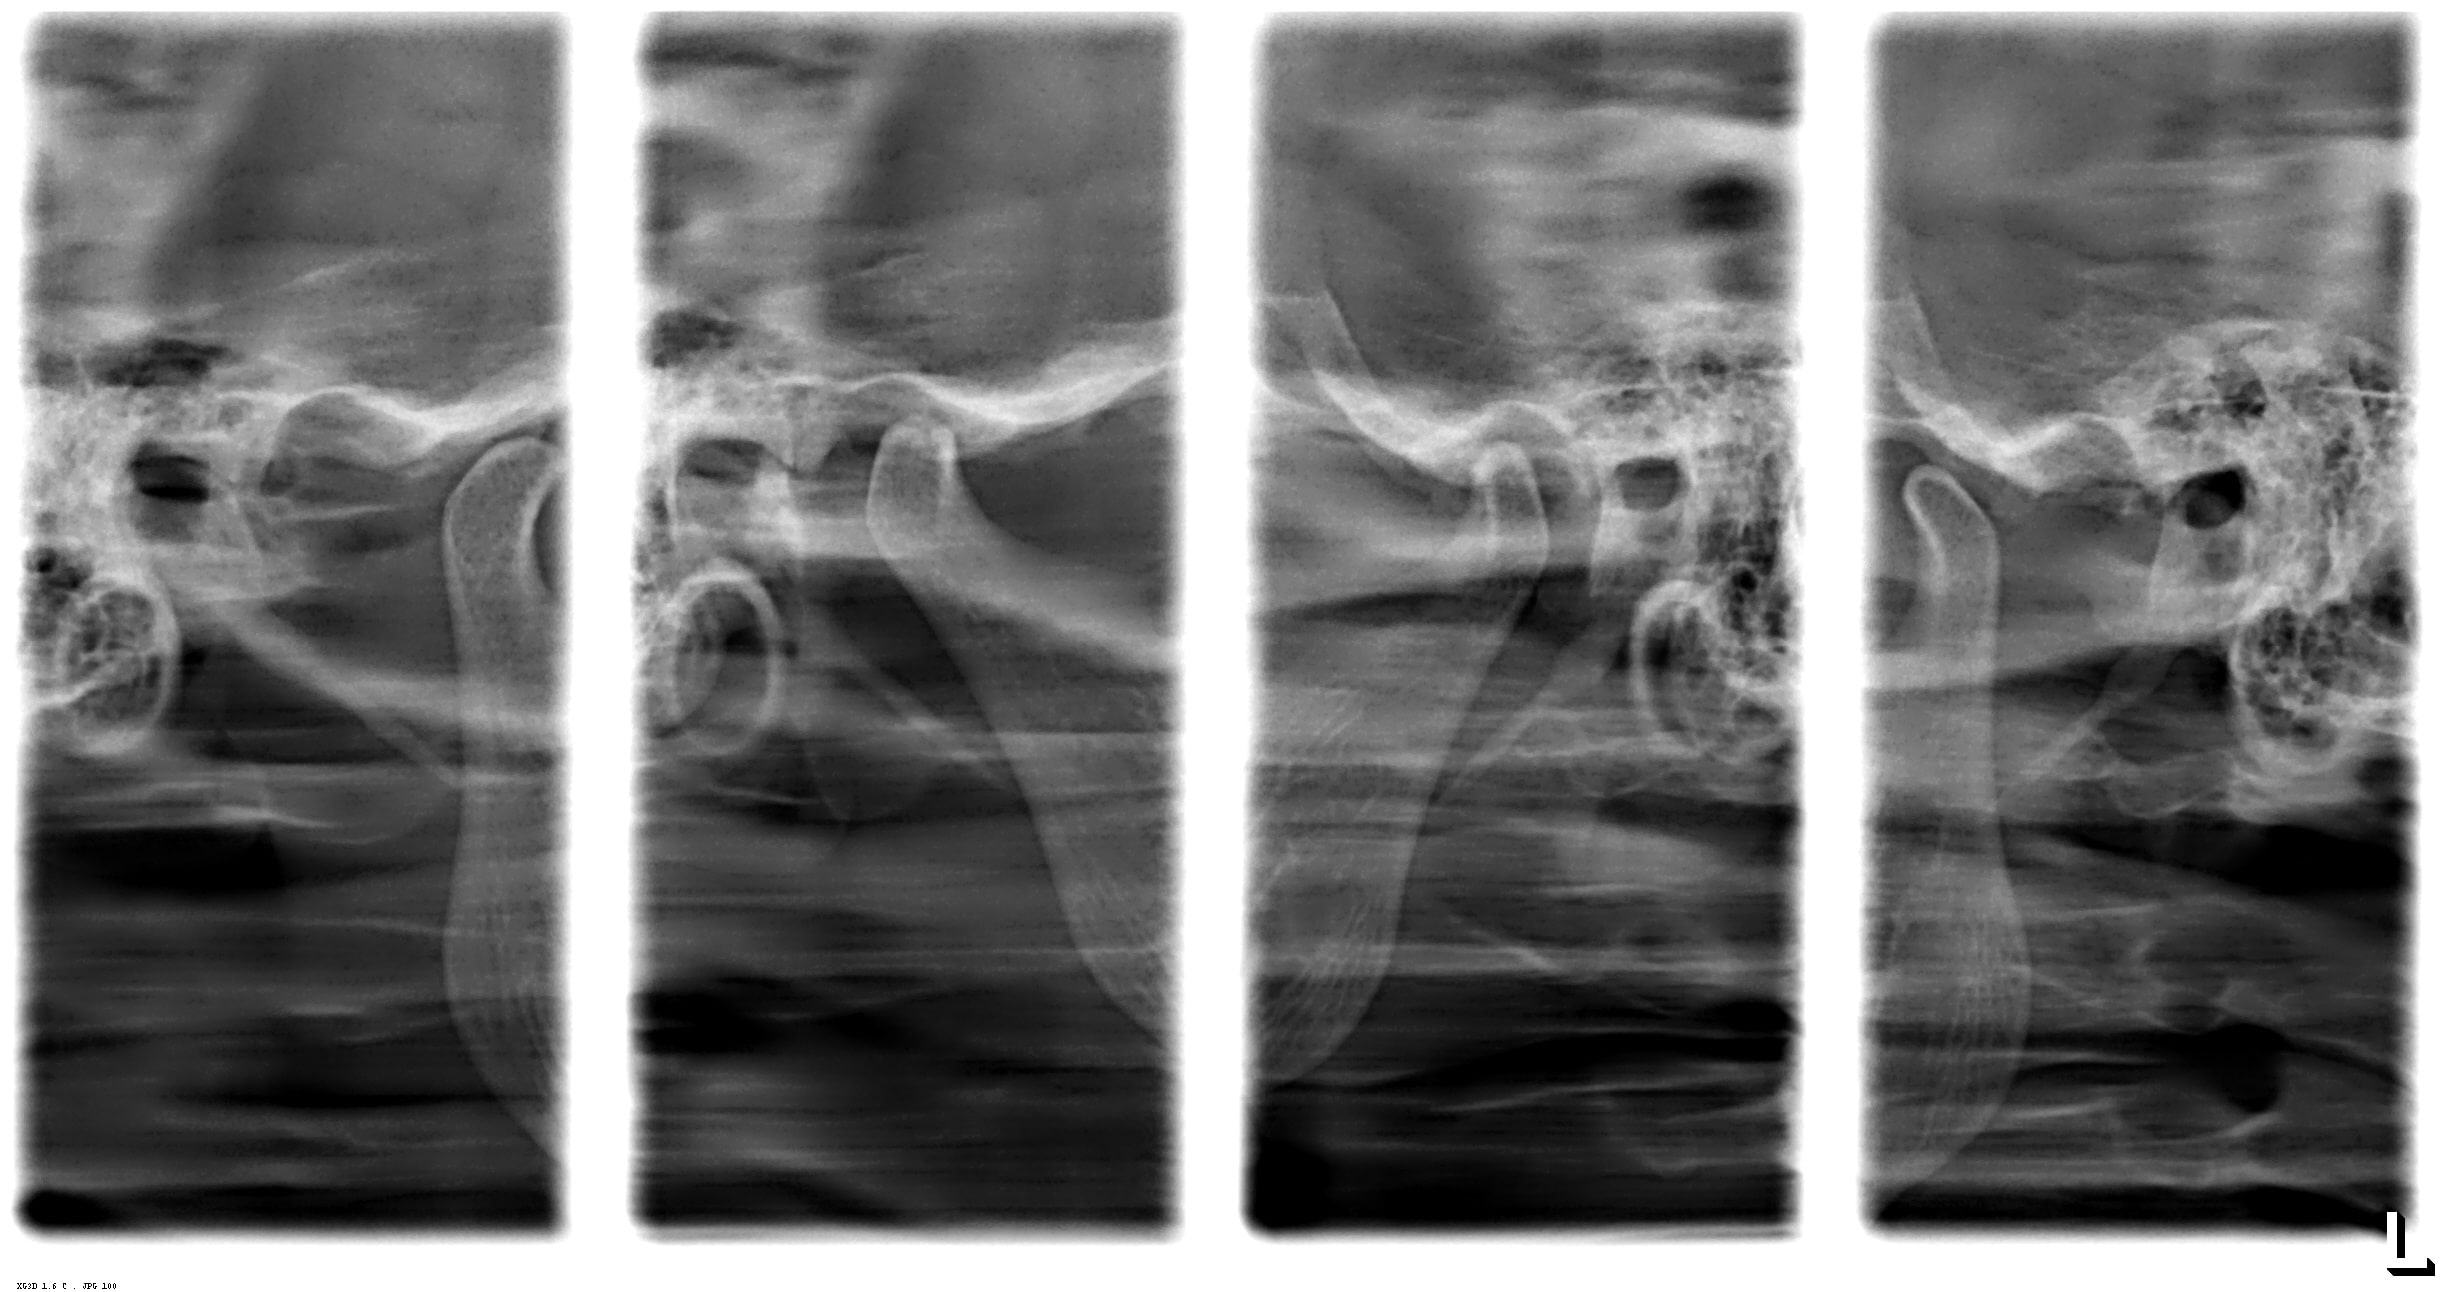

Radiografia de ATM (Boca Aberta e Fechada)